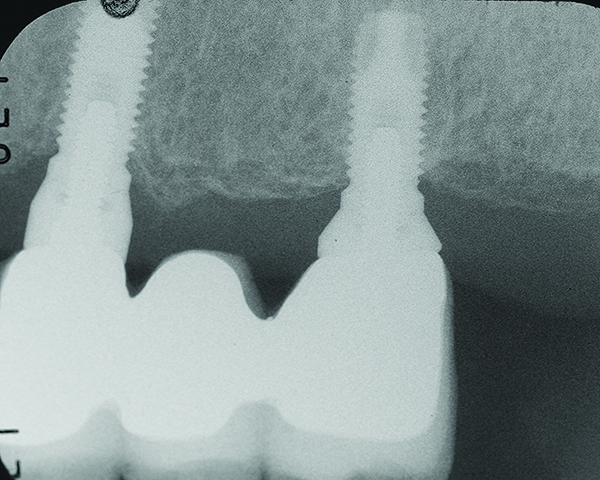

Fig 1 through Fig 6. Periapical radiographs of a 52-year-old man who received a fixed porcelain-fused-to-metal reconstruction supported by abutments attached to externally hexed dental implants. Fig 1 through Fig 3 are at initial prosthesis placement: maxillary right (Fig 1), textured surfaced threaded titanium implants at site Nos. 2, 4, and 6; maxillary anterior (Fig 2), implants at site Nos. 7 through 9; maxillary left (Fig 3), implants at site Nos. 12 and 14. Fig 4 through Fig 6 are 10 years post-insertion of the prosthesis: maxillary right (Fig 4), maxillary anterior (Fig 5), and maxillary left (Fig 6). Note minimal to no bone loss radiographically around the implants 10 years post-insertion of prosthesis.